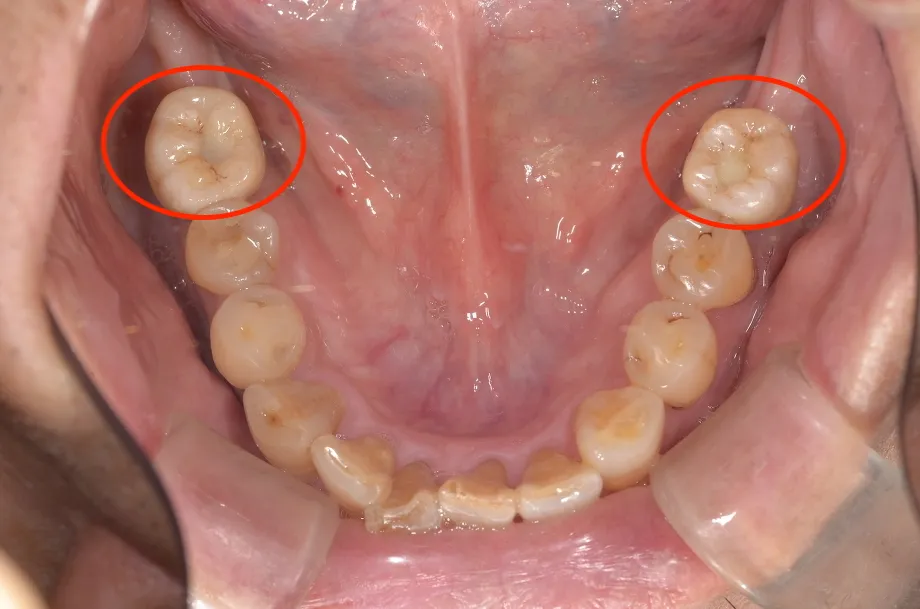

【噛み合わせ検査】

| ①CT解析検査 CTによる解析を行います。立体画像診断だけではなく、 『画像処理』ソフトも用いて、通常では確認しにくい骨の状況や血管・神経の配置を明確にします。 ②セファロ分析 骨格的な噛み合わせを分析し、理想に近いスマイルラインを形成します。 ③半調整咬合器による顎位診断 正しい顎の位置を特定する為、下顎運動を測定・解析し、骨格形態を分析します。 ④歯ぎしり・くいしばり検査 歯ぎしり・くいしばりの有無、力のかかり方を確認し、最適な治療に結び付けます。 | ★ CT解析![]() |

★ 顎位診断![]() |